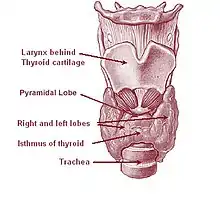

La thyroïde, moulée sur l'axe trachéo-laryngé, est de consistance ferme, de couleur rosée, et pèse de 25 à 30 grammes généralement mais en cas de goitre sa masse peut augmenter jusqu'à 100-150 grammes. Elle est entourée d'une capsule avasculaire (ou gaine viscérale péri-thyroïdienne) qui lui est propre et qui est différente de la loge thyroïdienne[1].

La thyroïde se compose de deux lobes droit et gauche situés verticalement de part et d'autre du larynx. Une partie intermédiaire horizontale, l'isthme thyroïdien, forme un pont entre les deux lobes. Généralement, la glande thyroïde répond aux 2e et 3e anneaux trachéaux ; mais elle peut avoir une position haute : 1er et 2e anneaux trachéaux, ou une position basse : 3e et 4e anneaux trachéaux. Les deux lobes ont un sommet supérieur, ainsi qu'une grande base inférieure. On leur décrit trois faces : médiale, postérieure et antéro-latérale. Sa hauteur est d'environ 6 cm pour une longueur de 6 à 8 cm. On trouve souvent entre les deux lobes, donc au niveau de l'isthme, le lobe pyramidal de Lalouette, souvent déporté vers la gauche : c'est un reliquat du canal thyréoglosse.

Il existe des variations morphologiques, s'expliquant par l'embryologie : en effet les deux lobes sont parfois éloignés l'un de l'autre sans qu'il n'y ait d'isthme, ou au contraire peuvent être soudés donnant une thyroïde en forme de V. Provenant d'un bourgeon de cellules endodermiques naissant près de la racine de la langue, différentes positions de la glande thyroïde peuvent cependant survenir durant l'ontogenèse : une mauvaise migration de cette ébauche conduit alors à la détection de cette glande (fonctionnelle ou non fonctionnelle) dans la région linguale, cervicale, voire endo-thoracique.